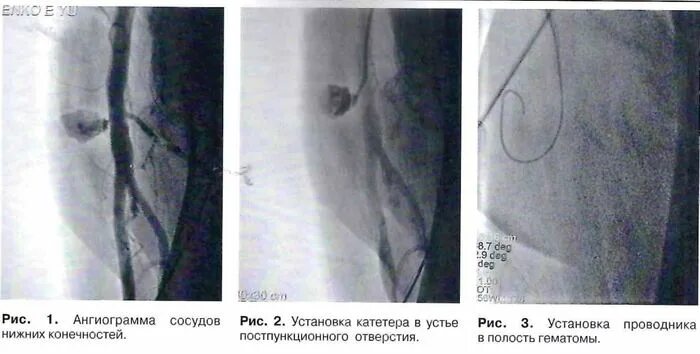

Постпункционная пульсирующая гематома. пульсирующая гематома узи. гематомы напряженные и пульсирующие. способ лечения постпункционной пульсирующей гематомы.

Пульсирующая гематома бедренной артерии. постпункционные гематомы. пульсирующая гематома и ложная аневризма. постпункционная пульсирующая гематома.